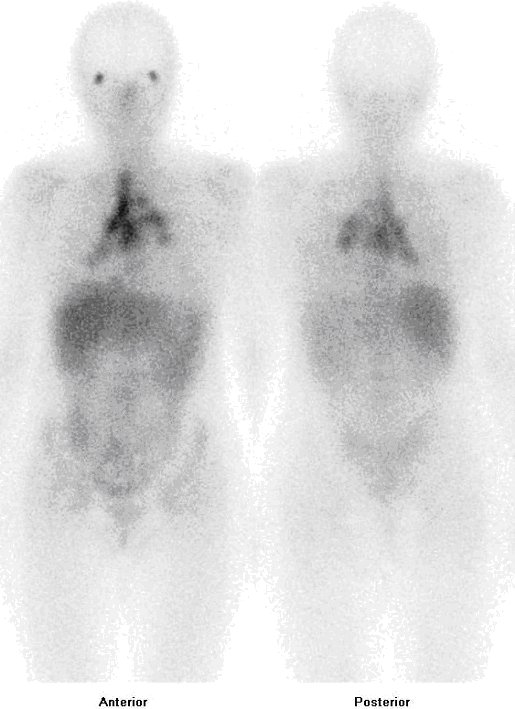

Byla provedena celotělová scintigrafie po aplikaci gallia. Po i.v. podání 200 MBq

citronanu gallitého (67Ga) (přípravku Gallium

(Ga67)Citrate injection firmy Mallinckrodt Medical) byla provedena celotělová scintigrafie pomocí dvouhlavé hybridní (SPECT/CT) scintilační kamery Symbia T2 firmy Siemens. Za 24 a 72 hodin po aplikaci gallia prokazujeme fyziologicky vyšší depozici radioaktivity difuzně v játrech, slezině, lehce v GIT a kostech, dále patologická ložiska v slzných žlázách a v plicích – v mediastinu a obou plicních hilech

(obr. 1, 2). Rozsah plicního postižení byl upřesněn pomocí cílené tomografické scintigrafie (SPECT) v kombinaci s CT

(obr. 3, 4, 5), nyní navíc zjišťujeme jedno ložisko v pravé plíci periferně.

/ Obr. č. 1: Celotělová scintigrafie po aplikaci gallium citrátu v přední a zadní projekci za 24 hodin po aplikaci.